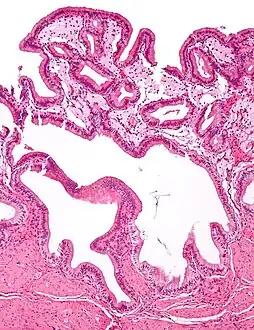

Cholesterolosis of gallbladder

Micrograph of cholesterolosis of the gallbladder, with an annotated foam cell. H&E stain.

In surgical pathology, strawberry gallbladder, more formally cholesterolosis of the gallbladder and gallbladder cholesterolosis, is a change in the gallbladder wall due to excess cholesterol.[1]

The name strawberry gallbladder comes from the typically stippled appearance of the mucosal surface on gross examination, which resembles a strawberry. Cholesterolosis results from abnormal deposits of cholesterol esters in macrophages within the lamina propria (foam cells) and in mucosal epithelium. The gallbladder may be affected in a patchy localized form or in a diffuse form. The diffuse form macroscopically appears as a bright red mucosa with yellow mottling (due to lipid), hence the term strawberry gallbladder. It is not tied to cholelithiasis (gallstones) or cholecystitis (inflammation of the gallbladder).[2]